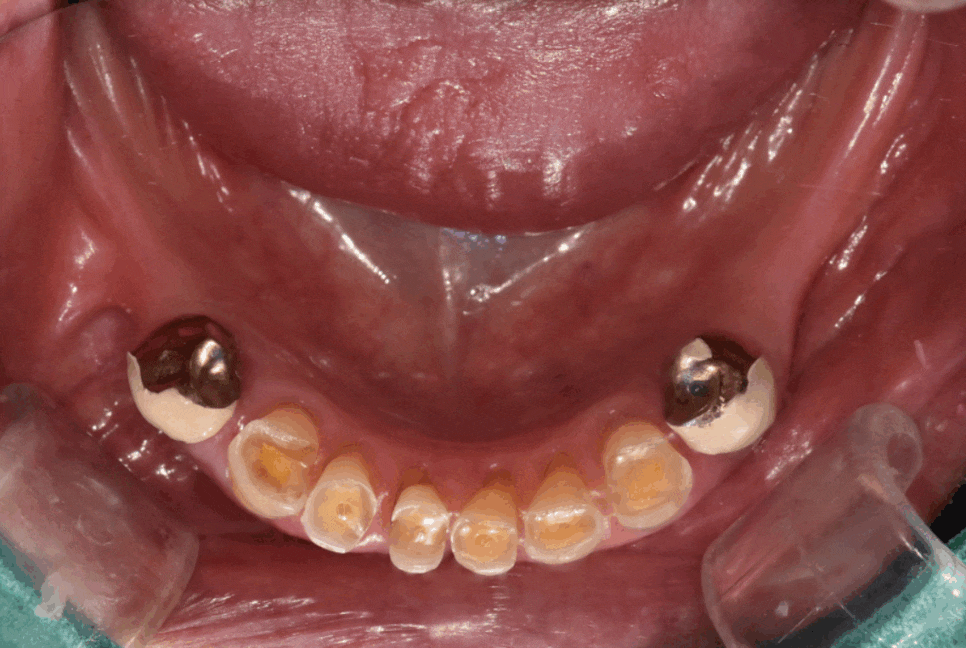

얼마 전 20대 중반 환자분이 오셨어요.

오른쪽 아래 어금니 잇몸이 자꾸 붓고

아프다고 하셨습니다.

확인해 보니 잇몸 쪽에 뾰루지처럼 나있네요.

250602